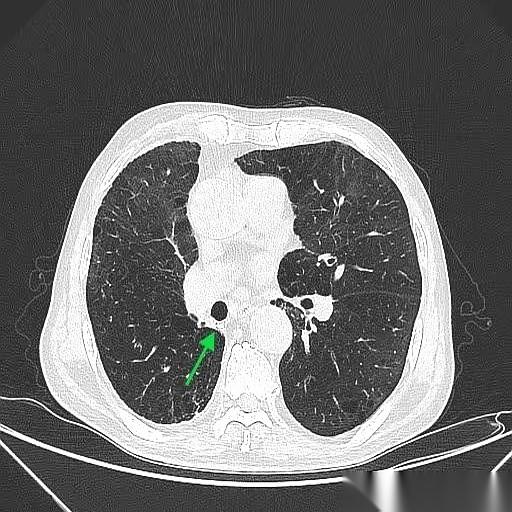

肺鳞癌,手术切完9年了,人活得好好的。 最绝的是,这大爷手术后烟都没戒。 真的,就是少抽了点。 说起来也邪门,当初救了他一命的,竟然就是他那要命的咳嗽和胸闷。要不是这俩症状把他折腾得受不了,跑去医院拍了个片子,那个藏在肺里2.4厘米的坏东西,还不知道要逍遥到什么时候。 一个抽了40年烟的71岁老爷子,你想想那犟劲儿。 手术很成功,切下来一看,万幸,早期,淋巴也没事。按理说,这都鬼门关前走一遭了,总该惜命了吧? 人家偏不。 就这么吊儿郎当地,九年过去了。 每年复查,啥事没有,肿瘤连个鬼影都见不着。有时候你真的会怀疑,老天爷是不是也有自己的KPI,专门考核戏剧性。 但命运这东西,总爱在结尾给你来个回马枪。 癌是没了,肺气肿倒是越来越厉害了。CT片子上,那肺啊,被烟熏得千疮百孔的。 老爷子今年终于又提了,说,准备戒烟。 也不知道这次是不是真的。 你说这人啊,有时候命硬得像块石头,有时候又犟得让人哭笑不得。 躲得过阎王爷,却好像总躲不过自己亲手点燃的那根烟。